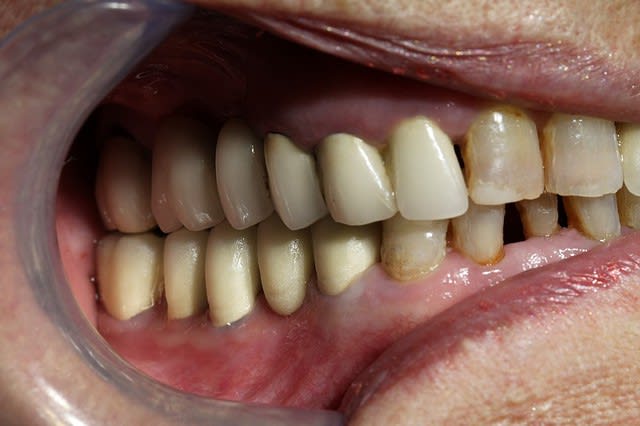

Cette même patiente, pimpante pour ses 90 ans et pleine de gaieté, viens me voir pour son nouvel appareil du bas qu'elle ne supporte pas. Avec surprise, je découvre dessous des chicots abandonnés par son ancien dentiste avec des inflammations gingivales. Radios prises, je lui propose de tenter de les récupérer pour lui réaliser des bridges en remplacement de son appareil, à l'inverse de ce qui se fait habituellement.

La racine résiduelle de la 37 était logée au fond d'un entonnoir gingival au ras de l'os et la 46 était trop délabrée pour la conserver entière. Après quelques séances de gingivoplasties et de tailles, le pari était gagné et les bridges ont pu être scellés, la patiente était radieuse!

Un autre type d'application en paro du CO² est son utilisation sans photo-ablation en défocalisant à faible puissance, ce qui entraine une cautérisation avec stérilisation, décongestionnement par évaporation de l'inflammation, sédation immédiate des douleurs et biostimulation.

Un exemple la semaine dernière: une patiente de 21 ans reçue en urgence pour un accident d'éruption de la 38 ayant entrainé une névralgie et un trismus avec ouverture limitée à 22mm.

Après utilisation d'un diode HeNe AsGa en mode myorelaxation, ce qui a permis une ouverture en quelques secondes à 30mm, un tir en balayage continu du CO² à 1W a fait disparaitre instantanément la douleur et a porté l'ouverture buccale à 40mm. Le tout a pris seulement quelques minutes.

J'ai alors pu lui prendre une radio et ai poursuivi sans problème par son premier détartrage, la jeune fille étant fumeuse (10 cigarettes par jour depuis 2 ans)... je suis alors tombé sur des leucoplasies au maxillaire que je n'aurai jamais découvertes sans l'aide de mes lasers ou avec une prescription d'AB et AI sans la revoir probablement, ses dents étant impeccables.

Je les lui ai montré et ai essayé de lui faire prendre conscience des risques qu'elle prenait en continuant à fumer sans l'affoler évidemment.